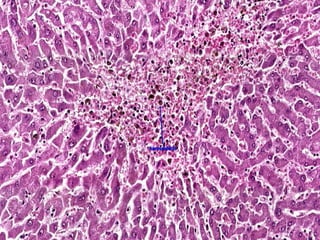

CVC Liver (MICRO) Bloodfills up the central vein & sinusoids around it. Followed by centrilobular hepatocyte atrophy and necrosis. In the long standing cases the necrotic area is replaced by fibrous tissue. The mid zonal hepatocytes may show fatty change due to relative hypoxia.  The areas with blood appears red & areas with fibrosis appears whitish yellow- NUTMEG APPEARANCE.

• #31 This view shows a close up of hemorrhagic central necrosis. Necrotic cells in the central area have been removed (cell dropout) and been replaced by cellular debris and hemorrhge. There is evidence that the passive congestion and hemorrhage is chronic, as many of the RBCs have been degraded into hemosiderin.